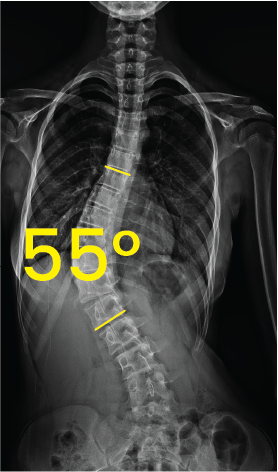

Omurga eğriliğini gösteren 55 derece açıyla skolyozlu gövde röntgeni.Göğüs bölgesinde 43 derece eğimli skolyozu gösteren omurga röntgeni görüntüsü.